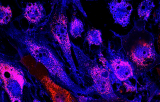

Les gènes du facteur de transcription 1 (RUNX1) et du partenaire 1 de la translocation RUNX1 (RUNX1T1) sont tous deux impliqués dans la régulation de la transcription des gènes au cours d'une hématopoïèse normale. La translocation non aléatoire t (8; 21) (q21.3; q22.1) est fortement associée au phénotype M2 franco-américano-britannique (FAB) et produit un gène chimérique constitué de la région 5' du gène RUNX1 fusionnée à la région 3' du gène RUNX1T1. On pense que la protéine chimérique est associée au complexe co-répresseur nucléaire / complexe histone désacétylase pour bloquer la différenciation hématopoïétique. L'hybridation in situ en fluorescence (FISH) peut fournir des informations importantes pour la gestion des patients souffrant de troubles hématologiques.